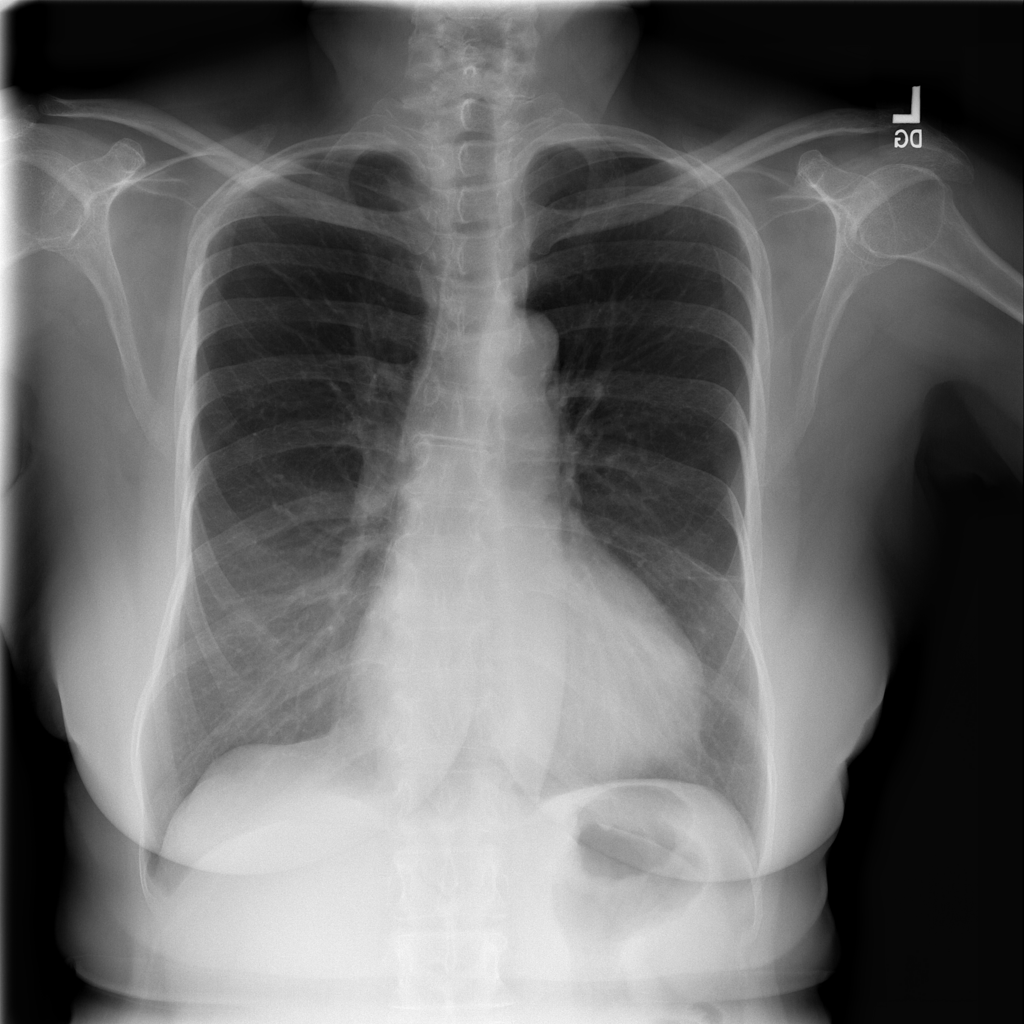

PAT-C255 · IMG-000Emphysema

PAT-C255 · IMG-000

PA